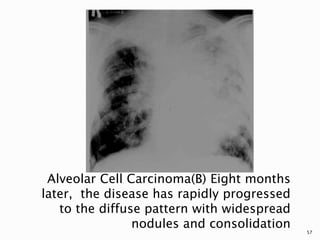

Alveolar cell carcinoma. (A) Chest X-ray

suggesting focal disease

Alveolar Cell Carcinoma(B) Eight months

later, the disease has rapidly progressed

to the diffuse pattern with widespread

nodules and consolidation 57